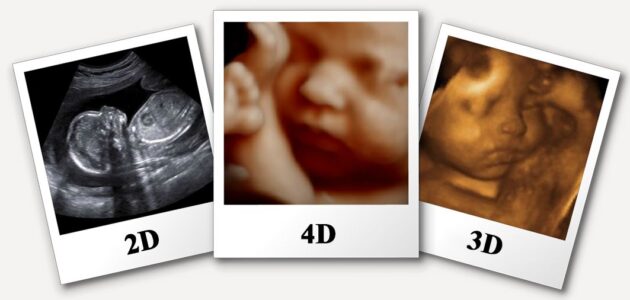

سونوگرافی دو بعدی: سونوگرافی دو بعدی، سونوگرافی سیاه و سفید است. این نوع از سونوگرافی در دوران بارداری جهت بررسی ساختار جنین و مراقبت های دوران بارداری انجام می شود.

- سونوگرافی سه بعدی: در این نوع از سونوگرافی دوران بارداری والدین جنین می توانند تصویر سه بعدی و واقعی از چهره جنین خود مشاهده کنند.

- سنوگرافی چهار بعدی: در این روش علاوه بر داشتن تصویری سه بعدی از جنین ، حرکت جنین هم قابل مشاهده است یعنی در لحظه انجام سونوگرافی می توان حرکت جنین را در شکم مادر رویت کرد.